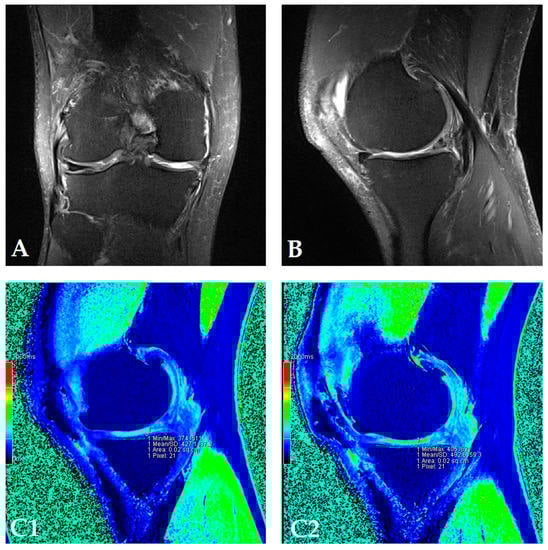

The dGEMRIC index was measured on seven different articular facets for each knee in the study, and the results are presented in a separate table for each patient (Supplementary Figures S1–S18). The dGEMRIC index was presented in absolute values, and the change of the index value through the study period is shown in percentages in relation to the baseline dGEMRIC index value. However, we observed that there was an increase in index value for the most articular facets after autologous and microfragmented adipose tissue injection. In 120 (53.57%) of 224 joint facets, we observed an increased dGEMRIC index 12 months after autologous and microfragmented adipose tissue injection. As expected, in cartilage lesions International Cartilage Repair Society (ICRS) grade IV, there were no changes in dGEMRIC value through the study period. In 33 (14.73%) joint facets, a decreased dGEMRIC index was found after 12 months in comparison with the baseline. Only in four (1.7%) of those was the decrease greater than 15% (highest in patient dG14, Figure S12). Those were joint facets with ICRS grade III and IV chondromalacia. For example, in patient dG15 (Figure 1D) with 4.4° varus deformity of the left knee, there was a 45% dGEMRIC index increase of the left lateral femoral condyle and an 83% index increase of the left lateral tibial condyle in comparison with the baseline. We also observed an increase of 13% and 3% for the lateral and medial patellar facet, respectively. However, the femoral trochlea index decreased by 4%. In patient dG07 (Figure 2D) with varus knee deformity (left knee 9.8° and right knee 3.5°), we observed a 26% increase of the index value in the medial condyle of the right tibia at the end of the study. Similarly, elevation was observed in other areas.

Figure 2.

(Patient dG07) Coronal (A) and sagittal (B) MRI show complete loss of articular cartilage of the medial femoral and tibial condyles (ICRS grade IV chondromalacia), thinning and shallow fissures of the articular cartilage in the lateral femoral and tibial condyles (ICRS grade IV chondromalacia), edge osteophytes and joint effusion. The MRI with the dGEMRIC index values at four-time points (T0: baseline; T3: three months after autologous and microfragmented adipose tissue injection; T6: six months after autologous and microfragmented adipose tissue injection; T12: 12 months after autologous and microfragmented adipose tissue injection) (C1–C4). The scheme of the dGEMRIC index with different joint facets throughout the study period at T0, T3, T6 and T12 combined with VAS scale ratings in T0, T3, T6, T12 (D).